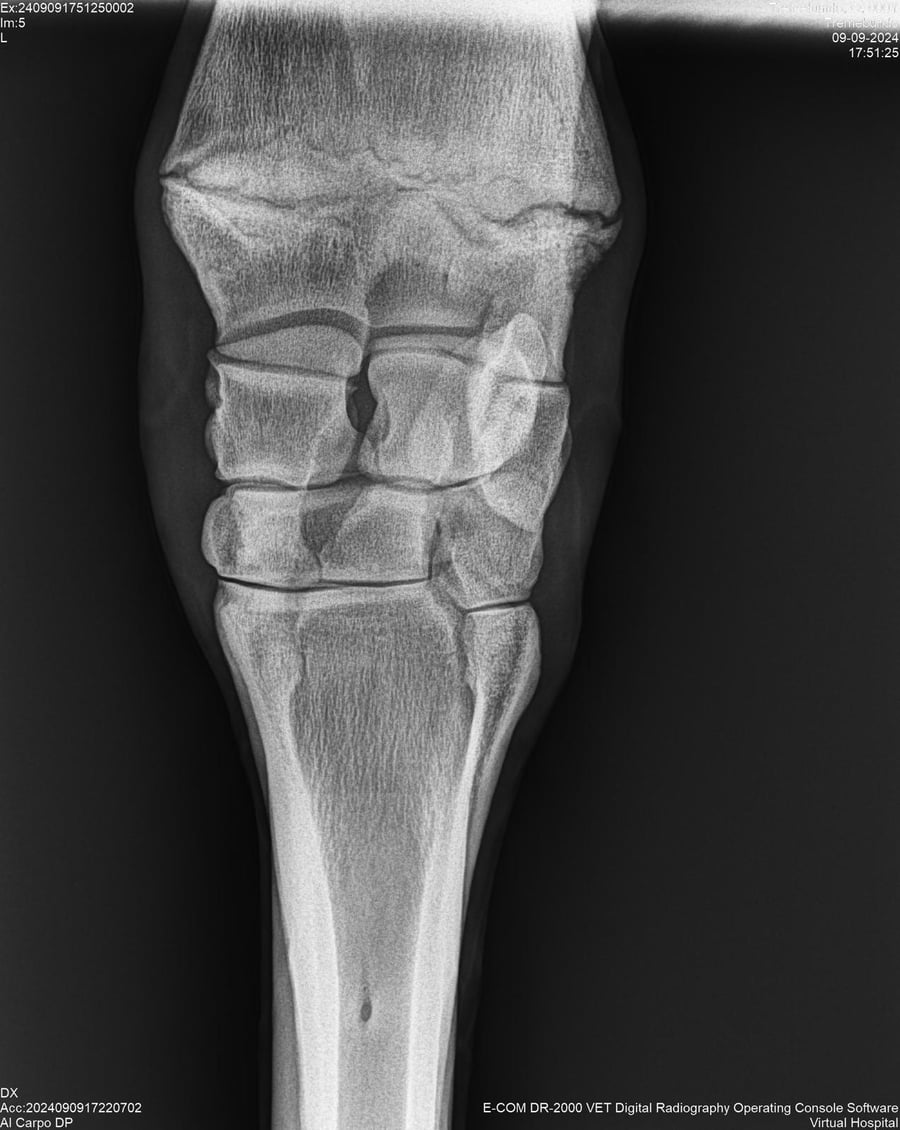

LOTE 37, TREMEBUNDO

Ficha del Lote

Identificador: #291140-

Generacion 2022